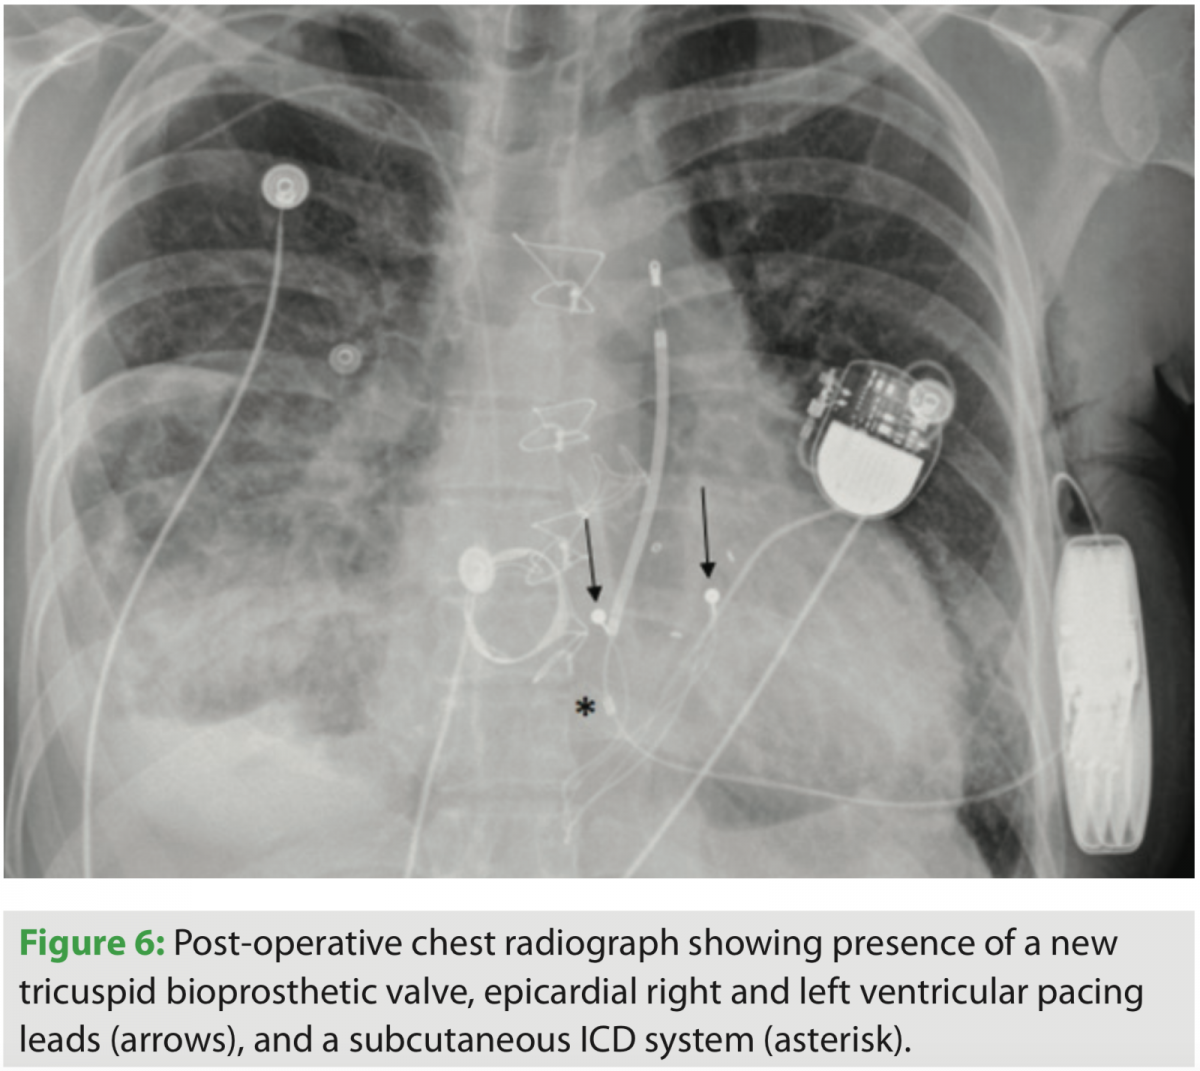

Ultimately, after careful consideration and discussion with the patient, we elected to proceed with a combined lead extraction of the transvenous ICD system, tricuspid valve replacement, and placement of an epicardial pacing system. We also elected to place a subcutaneous ICD system as a means of mitigating risk of sudden cardiac death. Immediate postoperative chest x-ray can be seen in Figure 6. The procedure was uncomplicated; however, it required several days of inotropic therapy to augment RV function. This was ultimately weaned, and the patient was discharged 11 days after surgery. In outpatient clinic follow-up, he remains euvolemic and has experienced a dramatic improvement in his HF symptoms.